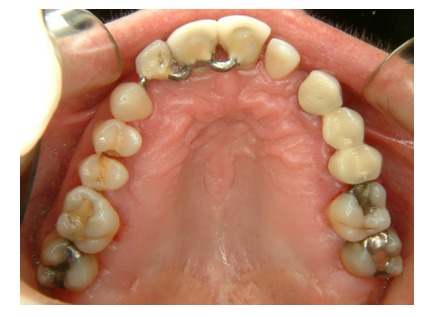

En la exploración intraoral deberemos examinar correctamente los rebordes edéntulos (morfología, anchura y altura de la cresta), la encía y sus características (color, textura, queratinización, un periodonto grueso es más favorable), la inserción de los frenillos, el vestíbulo oral, la lengua y el suelo de la boca. Además, valoraremos también el estado de los dientes remanentes,el grado de enfrentamiento de los rebordes antagonistas, la ubicación del paladar duro y blando, la posición de la papila interincisal, y el grado de apertura mandibular (ideal: 45mm, 3 dedos, 2 dedos representa el límite en implantología, menos impide la colocación de implantes en sectores posteriores) así como la presencia de abscesos u otras infecciones activas.

El papel del higienista en la toma de registros fotográficos es importante, teniendo en cuenta que la exploración por imagense ha establecido como un procedimiento de rutina, resultando un medio muy útil para el odontólogo dentro de supráctica clínica ya que es un excelente documento de la historia clínica que permite, sin la necesidad de tener presente al paciente, estudiar el caso, hacer el diagnóstico y establecer el plan de tratamiento en todo momento.

Para realizar una correcta exploración fotográfica, el higienista dental necesita colocar los retractores labiales o los espejos de fotografía intraoral y de esta forma reproducir perfectamente la zona a fotografiar. (Fig. 4)